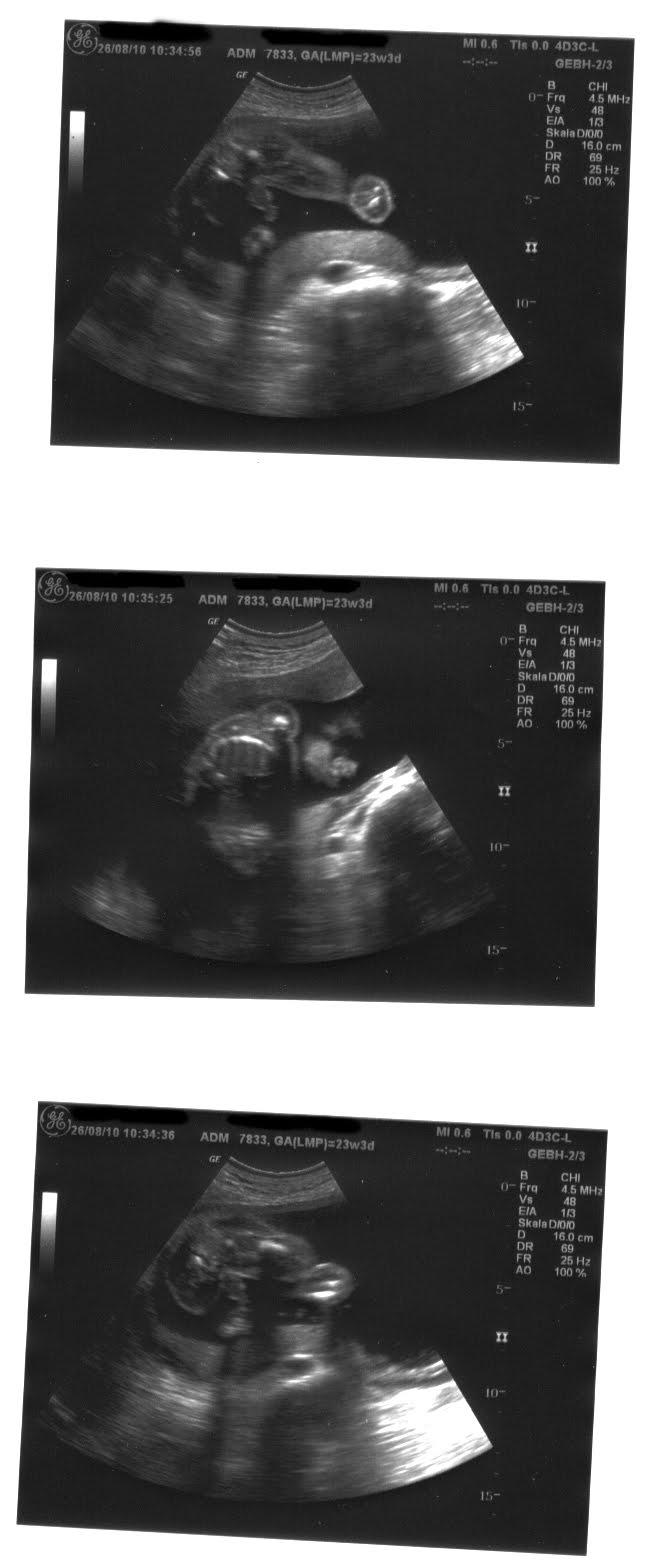

23 ssw mädchen outing. März 2019 um 15 06. Mädchen outing 18 ssw wie sicher. Ultraschall bilder mädchen oder junge oktober 2015. Outing 22 6 23 ssw 2017 18. Wohl ein indiz für einen jungen. Ultraschallbild madchen 21 ssw ultraschallbilder teil 2 mai 2016 babyclub seite 23. Wie sicher glaubt ihr daran ich dachte nur jungs sieht man so früh.

Ultraschallbild mädchen oder junge. Ich hätte zwar lieber ein mädchen gehabt aber dies kann man sich ja leider nicht aussuchen. März 2019 um 23 06. Was alles passiert ist und wieso ich ins krankenhaus musste. Geschlechterraten per ultraschall januar 2015 babyclub. Wann kann man per ultraschall das geschlecht erkennen. Seite 1 forum.

Schwanger wer noch. Ssw 23 ich kann nicht nachvollziehen wenn mir jemand sagt dass ich noch sooo ein kleines bäuchlein habe. Ultraschallbild 14 ssw mädchen ultraschallbilder mehr als 50 bilder aus der schwangerschaft. Mädchen outing 16 3 ssw 8. Mir wird richtig oft erklärt dass man bei mir noch gar keinen bauch sieht also klar unter weiter kleidung ist das halt so.